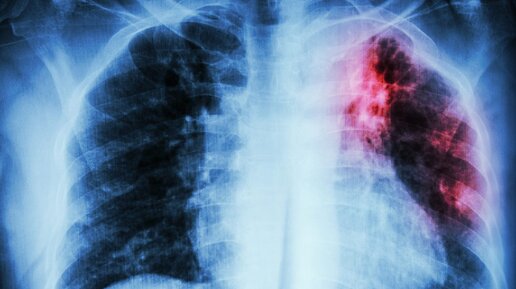

Первые признаки открытой формы туберкулеза, как обнаружить и как вылечиться?

Одной из самых распространенных инфекций в современном нам мире является туберкулез. Возбудителем этой патологии является палочка Коха. Ее опасность заключается в том, что заразиться можно воздушно-капельным путем, то есть при обычном контакте с человеком. Больной человек особенно опасен для других, если патология протекает в открытой форме, так как вместе с его мокротой выделяется большое количество микобактерий. Особенно опасна открытая форма туберкулеза для людей с низким иммунитетом. Туберкулез, при котором происходит постоянное выделение микобактерий во внешнюю среду, называется открытый...